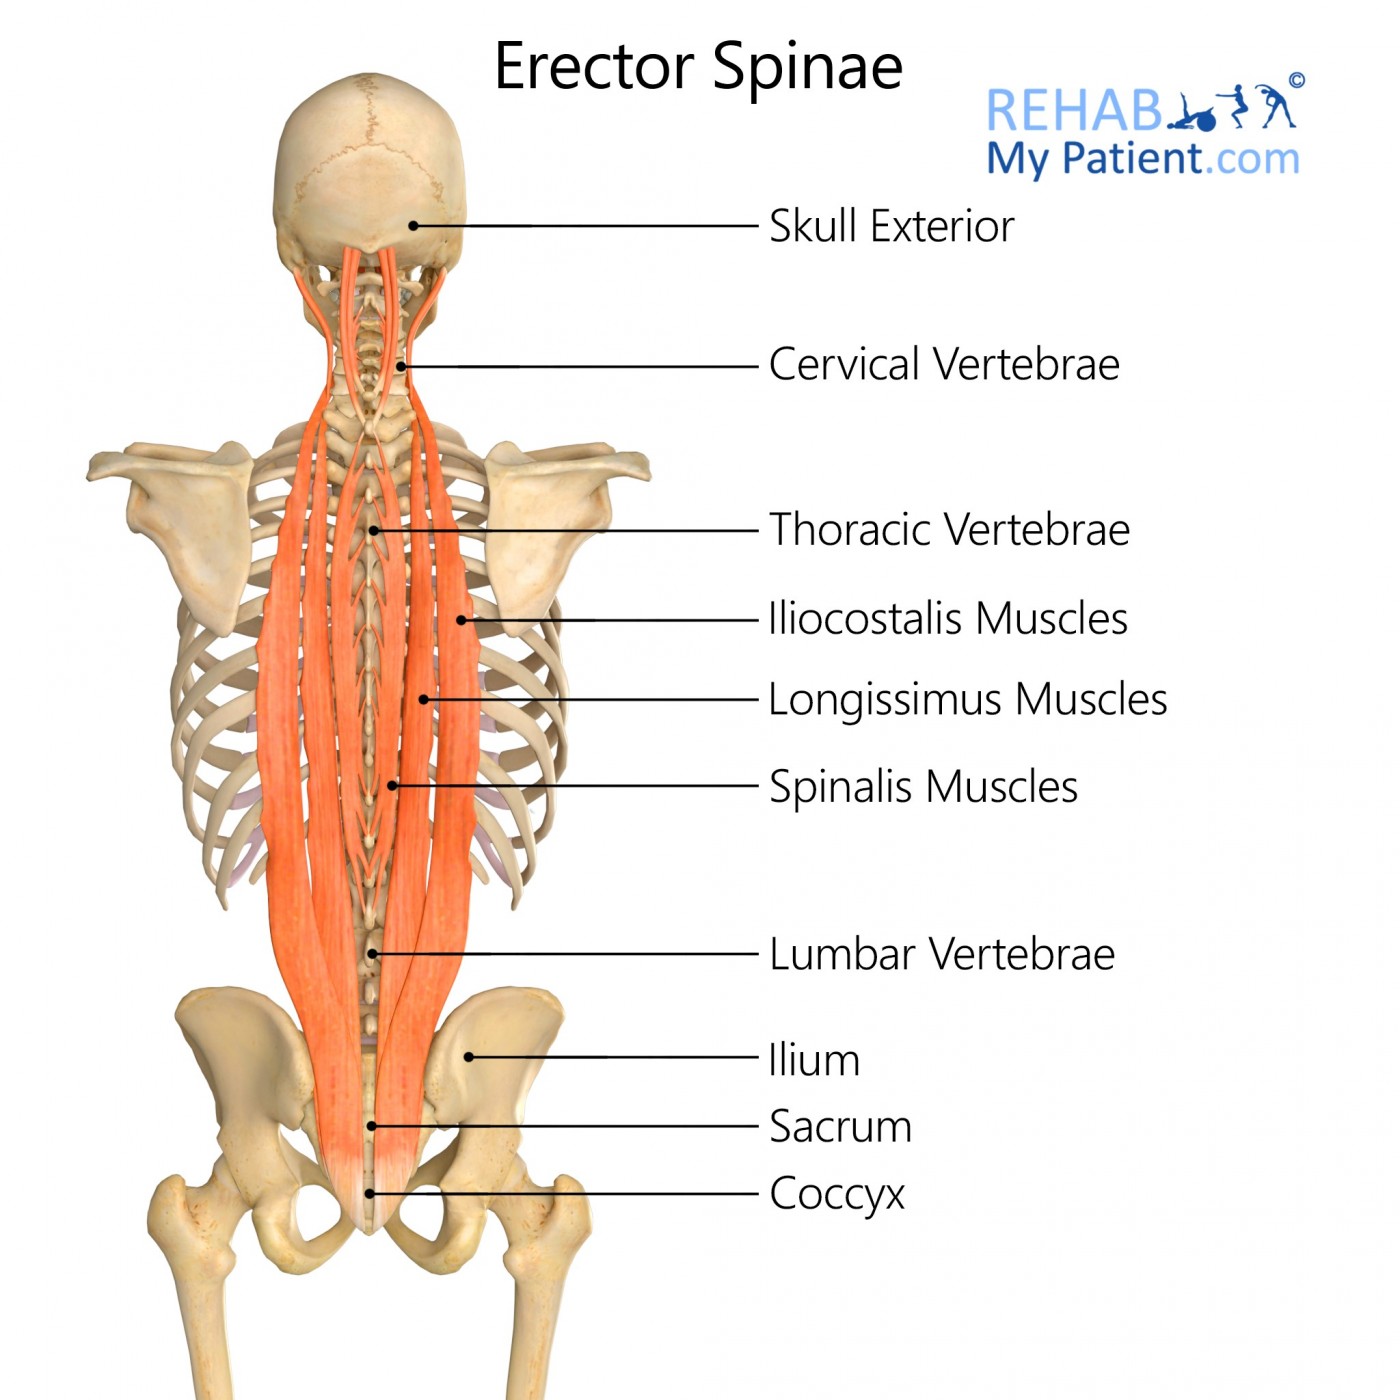

Erector Spinae Exercises